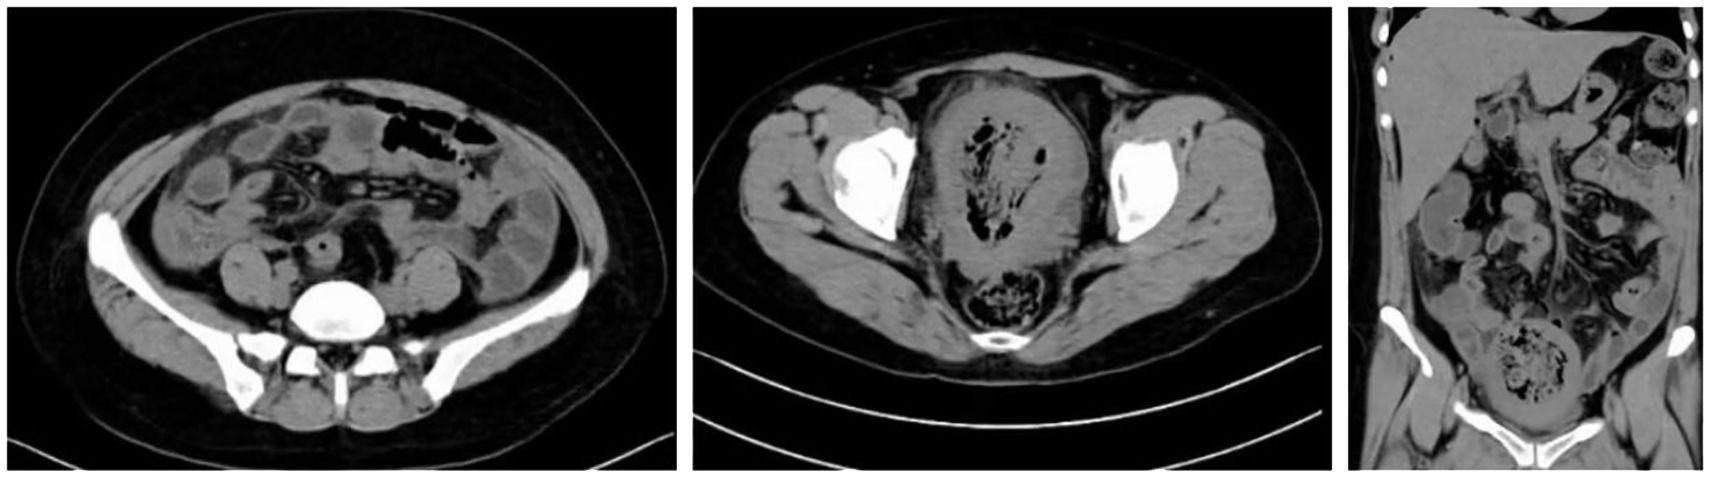

Background: High-intensity focused ultrasound (HIFU) ablation is widely regarded as a safe and minimally invasive technique for treating uterine fibroids. However, severe complications such as uterine rupture and septic shock remain exceedingly rare. Case presentation: We report a case of a 42-year-old woman who developed uterine rupture complicated by septic shock one month after undergoing HIFU ablation for uterine fibroids. Conclusions: Although HIFU ablation for uterine fibroids is widely considered a safe and minimally invasive procedure, clinicians should recognize the potential for severe complications, including uterine rupture and septic shock.